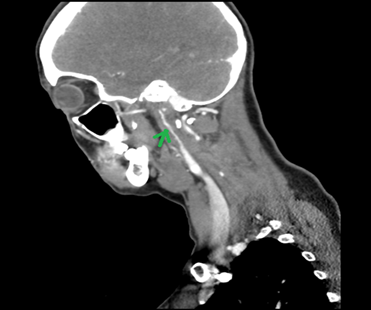

nihss of 8. A ct angiogram (cta) of the aortic arch and carotids (and

intracranial vessels) was performed as all her symptoms were within 6 hours of

time of onset. The cta (figure 1) revealed right internal carotid artery

dissection 17 mm past carotid bifurcation. No large vessel occlusion of both

extracranial and intracranial vessels was found.

Figure 1: right ica

dissection on ct angio (arrow). Rat tail appearance due to reduced lumen size

of blood vessels because of dissection